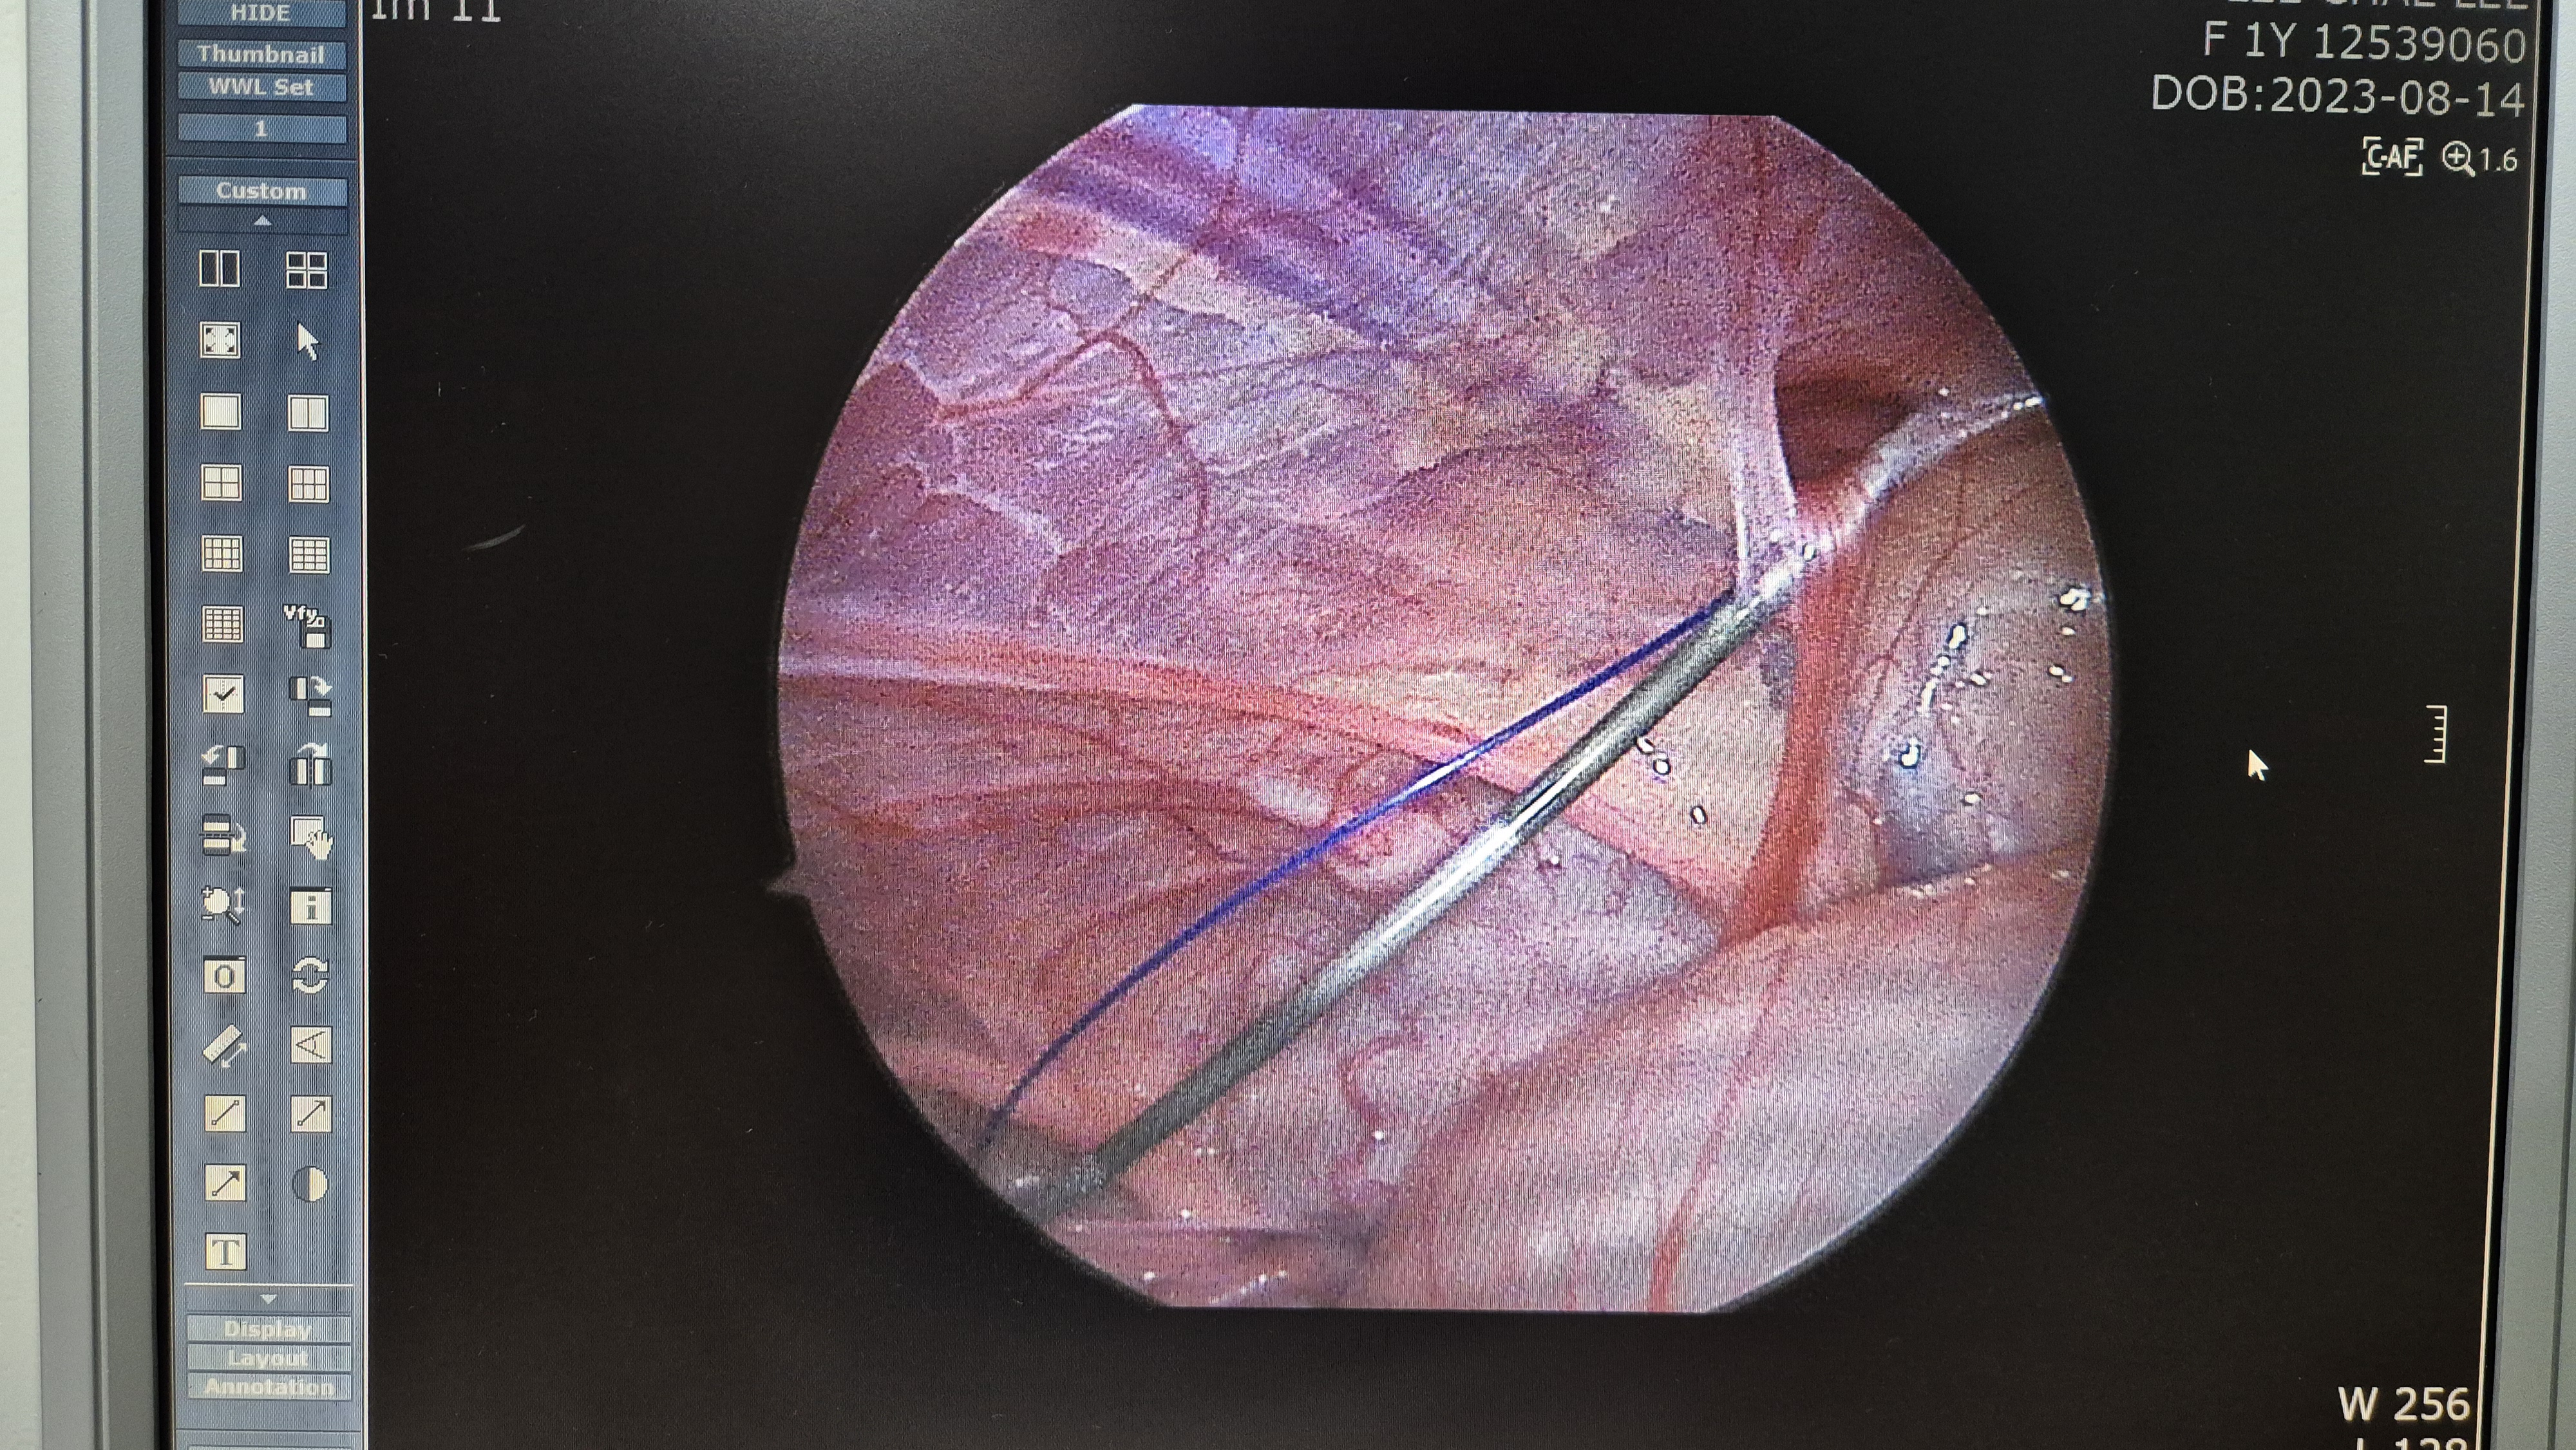

탈장 교정중.